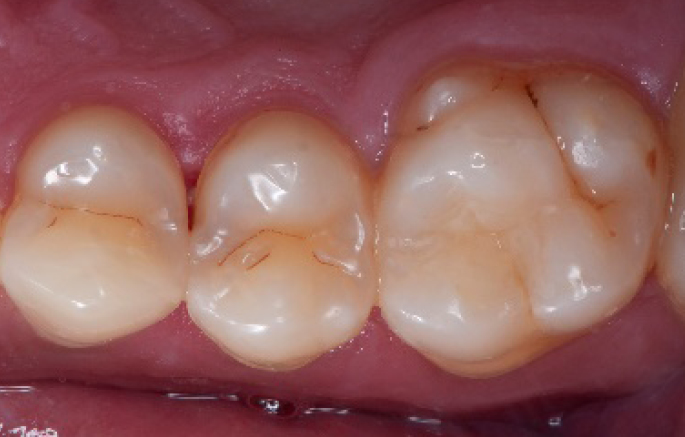

After

Final situation 2 weeks after the filling. Great comfort and no sensitivity at all were reported by the patient.

The situation after rubber dam removal.

2 weeks control